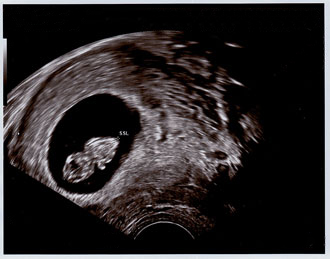

Endlich auch dabei! - Tagebücher aus der Schwangerschaft von Julia aus Göttingen